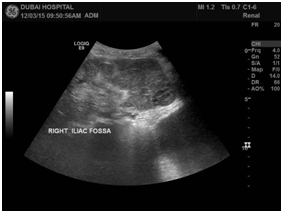

Over a few months, he was complaining of intermittent haematuria with a bulge noticed at the right lower loin, Ultrasound was done in April 2015; and revealed a big mass in the right old transplant kidney (see image 1A, 1B). CT scan with contrast was done (image 2A, 2B), and revealed a large lobulated outlines heterogeneously enhancing mass arising from the right iliac fossa of the transplanted kidney (measures 8.7x 6.9x11.5cm in diameter) with local invasion, lungs metastasis and right common iliac vein tumor thrombus. Due to above finding patient underwent right allograft nephrectomy, with uneventful post-operative course. Biopsy of the transplanted kidney consists with clear renal cell carcinoma. His immunosuppression had been modulated by stopping Mycophenolate and replacing cyclosporine by Everolimus. He is also under oncology follow up (Figure 1a,1b & 2a,2b).

Figure 1a&1b: Old Transplanted kidney in the right iliac fossa shows a large hypoechoeic solid lobulated mass measuring 10.0x6.9cm with increased vascularity on Doppler.